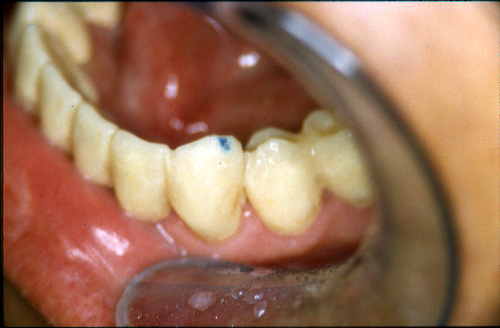

ABSTRACT El Bruxismo es una entidad patológica en la que concurren diferentes factores. Entre ellos el stress que conlleva consigo la vida moderna, constituye el Factor Predisponente sobre el que se ha abundado en innumerables tratamientos de tipo general, actuando sobre la psiquis y el comportamiento del individuo, ya sea con fármacos o bien mediante medios psicológicos. Sin embargo, como tantos desequilibrios provocados por el stress, confluyen siempre con un Factor Desencadenante, que en el caso del Bruxismo se encuentra en las desarmonías entre los componentes varios del Sistema Estomatognático. DESARROLLO Paciente varón, de 43 años, constitución atlética. A la inspección se observan desgastes oclusales que alcanzan la calidad de Facetas Parafuncionales, con dentina expuesta y empastes totalmente gastados y evidentes signos de falta de Disclusión Canina de ambos lados. Sobre dicho montaje se realiza un Encerado Progresivo de Diagnóstico, aportando en el mismo los elementos necesarios para obtener todos los principios básicos de una Oclusión Orgánica. FIG. 6 a 24 Una vez aprobado el fisiologismo de la oclusión en el articulador, se reproducen modelos de yeso con la nueva situación, y se estampa un SET UP en cada maxilar. FIG. 25/26 Procedemos entonces al tallado de las piezas correspondientes a la Guía Anterior, y rebasamos los estampados, creando en boca una nueva situación desoclusiva, que permanece en boca durante los pocos días que transcurren entre la primera y segunda visita de trabajo. FIG. 27/33 Ya abordando en esta segunda visita los sectores posteriores, tanto superiores como inferiores, tallamos siempre de manera supragingival, destacando la importancia vital de la forma obtenida en las provisionales, a las que abrimos plenamente las troneras para lograr una correcta higiene. FIG.34 a 43 FIG. 44 a 52 Efectuados los colados en oro y probados en boca, en el laboratorio se confecciona el bizcochado de la nueva Guía Anterior, la que puede o no copiarse de la Guía Anterior provisional, mediante la técnica denominada Trayectoria Funcionalmente Generada, que consiste en realizar en la platina del articulador un registro estereográfico sobre acrílico Duralay en polimerización. FIG. 57/58 Ajustados todos los detalles mediante esta técnica, se instala en boca en forma Provisional y se deja funcionando una semana o dos, al cabo de las cuales se chequean las disclusiones , los ajustes, la eficacia masticatoria, la carencia de sintomatología articular y muscular. FIG.59 a 63 PIE DE FOTO FIG.9 OBTENCIÓN DE LA GUÍA ANTERIOR FIG.10 Y 11 PITOMBOS. ALINEAC. TRIDIMENSIONAL FIG.12 PITOMBOS. DISCLUSIÓN DER. FIG.13 PITOMBOS. DISCLUSIÓN IZQ. FIG.14 WILSON INF. FIG.15 WILSON SUP. FIG.16 BOCA DE PEZ INF. FIG.17 BOCA DE PEZ SUP. FIG.18 VISTA OCLUSAL FIG.19 O.R.C. FIG.20 DISCLUSIÓN DERECHA FIG.21 CRESTAS TRIANG. INT. FIG.22 CRESTAS TRIANG. INT. FIG.23 CRESTAS TRIANG. INT. FIG 24 CRESTAS TRIANG. INT. FIG.59 DISCLUSIÓN IZQ. FIG.60 DISCLUSION IZQ. FIG.61 DISCLUSIÓN DER. FIG.62 DISCLUSION DER. FIG. 63 AJUSTE PERIFÉRICO